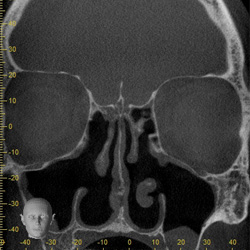

Volumenbestimmung

der Kieferhöhlen